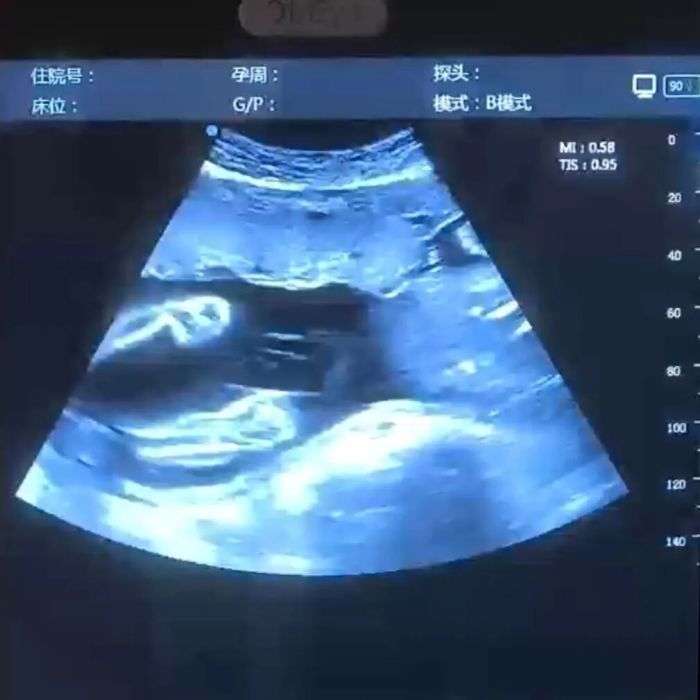

✅动态影像留存:每次检查,我们不仅解读健康(成长)数据,更会精心录制宝宝在妈妈子宫里的实时动态——翻身、吮吸、踢腿,甚至打个哈欠,都为您剪辑成专属视频。

宝宝在“跳舞”

宝宝在跟妈妈打招呼

在医生指导下,您和家属将通过高清大屏幕实时看到宝宝的一举一动。检查过程中,医生会同步讲解宝宝的发育情况,让您更懂宝宝的“悄悄话”。

检查结束后,工作人员会将录制的动态影像进行专业剪辑,配上舒缓的背景音乐,生成一段3-5分钟的“宫内成长微电影”。同时精选关键照片,排版设计成纪念册初稿。